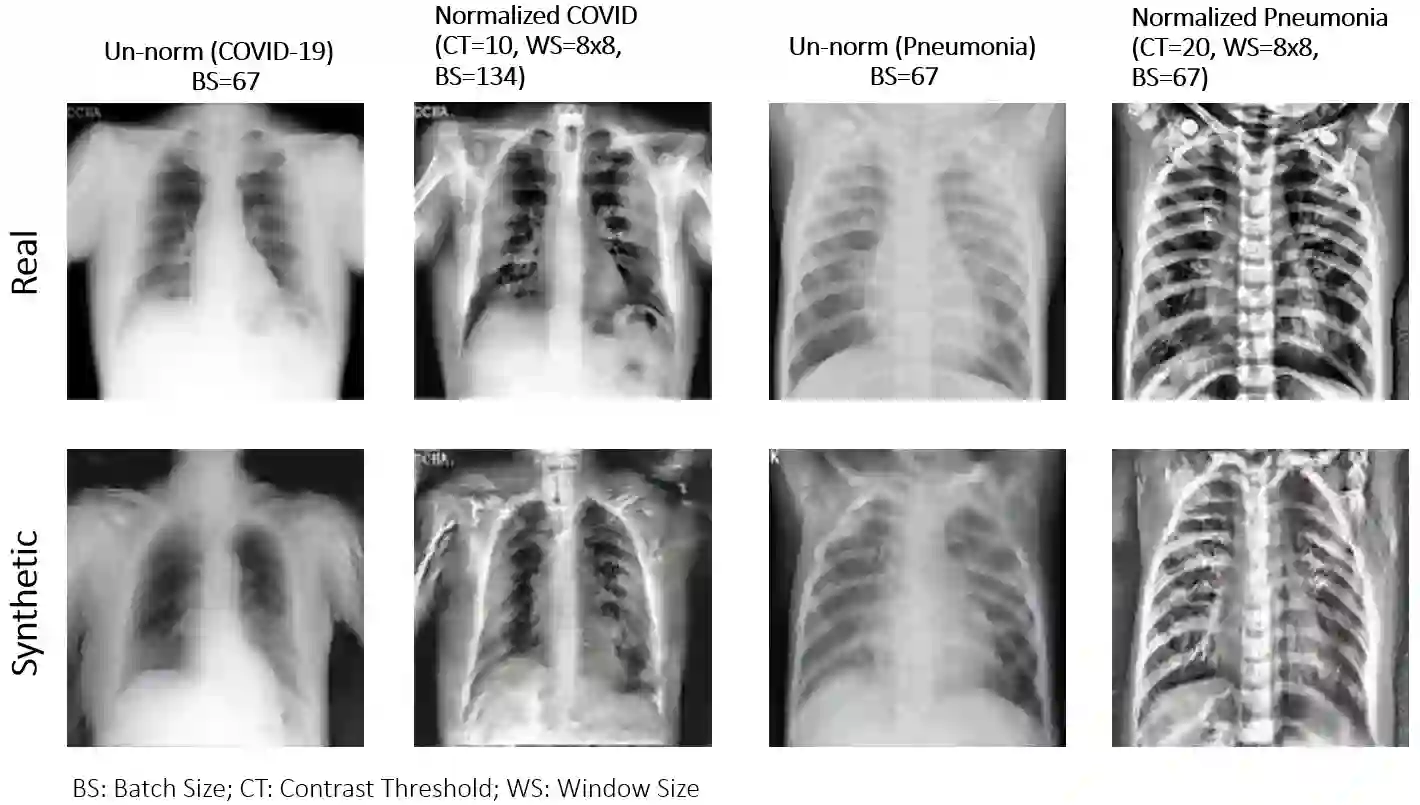

Biomedical image datasets can be imbalanced due to the rarity of targeted diseases. Generative Adversarial Networks play a key role in addressing this imbalance by enabling the generation of synthetic images to augment datasets. It is important to generate synthetic images that incorporate a diverse range of features to accurately represent the distribution of features present in the training imagery. Furthermore, the absence of diverse features in synthetic images can degrade the performance of machine learning classifiers. The mode collapse problem impacts Generative Adversarial Networks' capacity to generate diversified images. Mode collapse comes in two varieties: intra-class and inter-class. In this paper, both varieties of the mode collapse problem are investigated, and their subsequent impact on the diversity of synthetic X-ray images is evaluated. This work contributes an empirical demonstration of the benefits of integrating the adaptive input-image normalization with the Deep Convolutional GAN and Auxiliary Classifier GAN to alleviate the mode collapse problems. Synthetically generated images are utilized for data augmentation and training a Vision Transformer model. The classification performance of the model is evaluated using accuracy, recall, and precision scores. Results demonstrate that the DCGAN and the ACGAN with adaptive input-image normalization outperform the DCGAN and ACGAN with un-normalized X-ray images as evidenced by the superior diversity scores and classification scores.